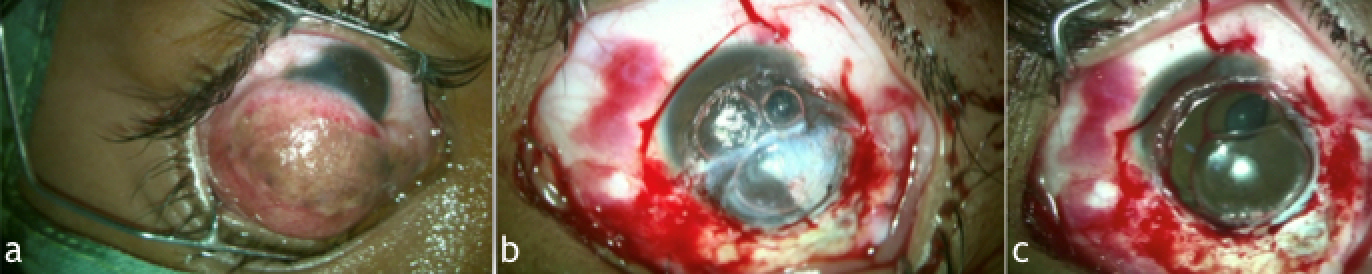

Surgery was conducted under local anaesthesia, and dermoid excision (Figure 2a [Fig. 2]) was initiated. Limited conjunctival peritomy was done superior and temporally, and blunt dissection of the lesion was carried out. Lamellar dissection of the lesion from the cornea was done with a crescent blade. However, deep extension of the dermoid in the posterior stromal layers was noted (Figure 2b [Fig. 2]), which lead to a change of plan from ALK/amniotic membrane grafting to manual pre-descemetic DALK. Manual dissection was carried out to expose the Descemet’s membrane (Figure 2c [Fig. 2]). After this, a donor tissue 9.5 mm in size was prepared by scraping the endothelium and trephine. Thereafter, the tissue was secured with the host with a 10-0 nylon suture (Figure 3a [Fig. 3]).

Figure 2: Intra-operative pictures showing (a) limbal dermoid sparing superior one-third of the cornea; (b) deeper involvement of corneal layers visualized after dermoid excision; (c) Descemet’s membrane was exposed after manually dissecting deeper stromal layers.